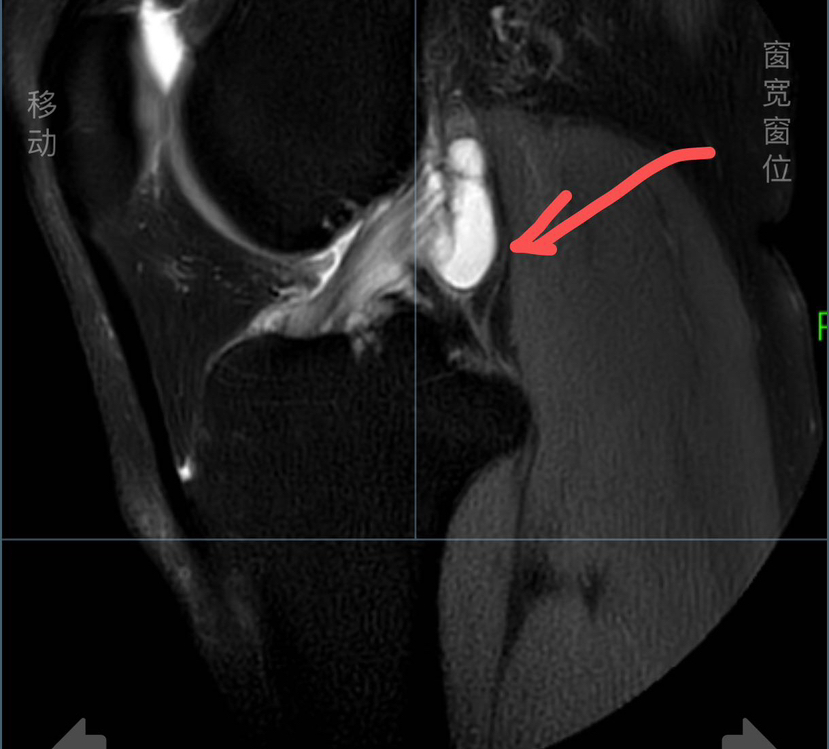

【 个别情况下韧带巨大囊肿完全或大部分侵蚀韧带,清理囊肿后,韧带纤维不多,不足以维持膝关节稳定,这种情况下需要进行韧带重建!

(囊肿巨大完全侵蚀韧带)